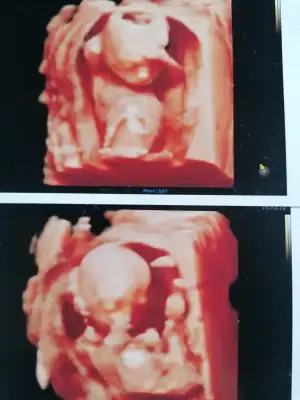

Canım erken bence garanti olsun diye 16.haftadan önce gitmeBende aynı durumdayım 14. Haftamdayım doktorum izinde benimde başka doktora gitçdersin bu ay çok merak edersen cinsiyeti dedi ama ne zamma gideyim çok kararsızım